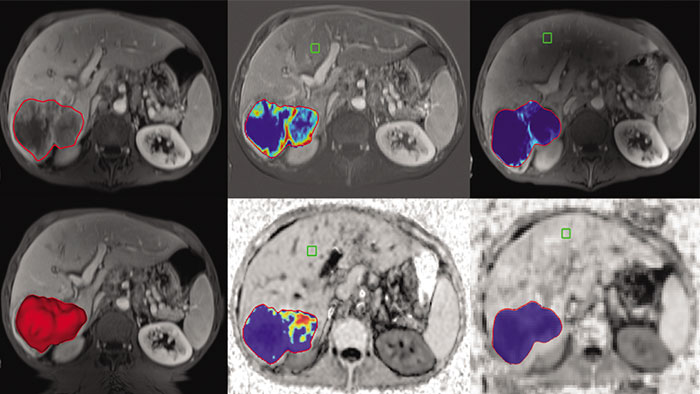

Computed diffusion weighted images at a b-value of choice

The application is intended to view, process and analyze MRI Diffusion Weighted Images. It calculates and displays cDWI at a

b-value of choice (from 0 to 5,000 s/mm2) and provides advanced supportive analysis and visualization tools of diffusion MRI images and parametric maps.